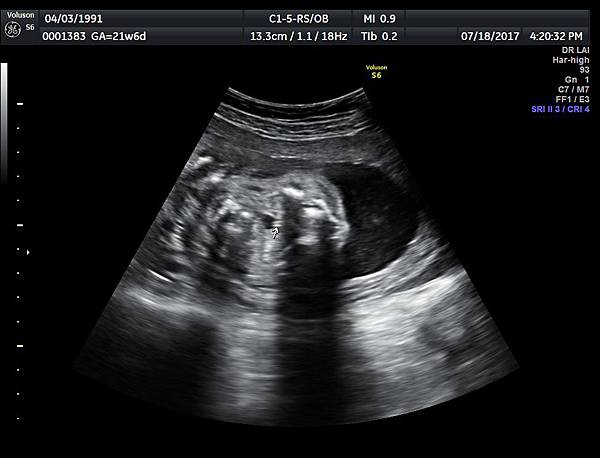

21w 6d right side cleft lip and palate and cleft uvula and brain anomaly < ACC and lissencephaly> images 3421

一個檢查如果要花很長的時間才能完成,這樣的檢查無法變成常規的篩檢方式,我已經在我的診所執行懸雍垂檢查一段時間,我檢查懸雍垂大約30 秒,前提是胎兒的臉最佳位置是側躺,其次是側躺偏向上,我的檢查步驟是上顎(含日後大門牙長出的位置)、舌頭、懸雍垂(= equal sign)(附圖1~8),如果超過60秒無法完成,只有兩個原因,一個是胎兒姿勢不適合或喉嚨羊水空間太小,這時候不要硬碰硬,只要先檢查其他部位,等待時機再回來即可,我的經驗是90%的cases都能順利完成這項檢查(肚皮厚的case真的是很難)。